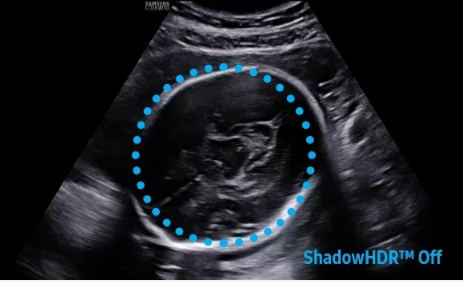

2D成像方面,Hera i10集成了包括ShadowHDR?、HQ-Vision?、ClearVision等多項具有三星“血統(tǒng)”的技術(shù),加強了圖像的陰影抑制、減少偽影、緩和模糊區(qū)。